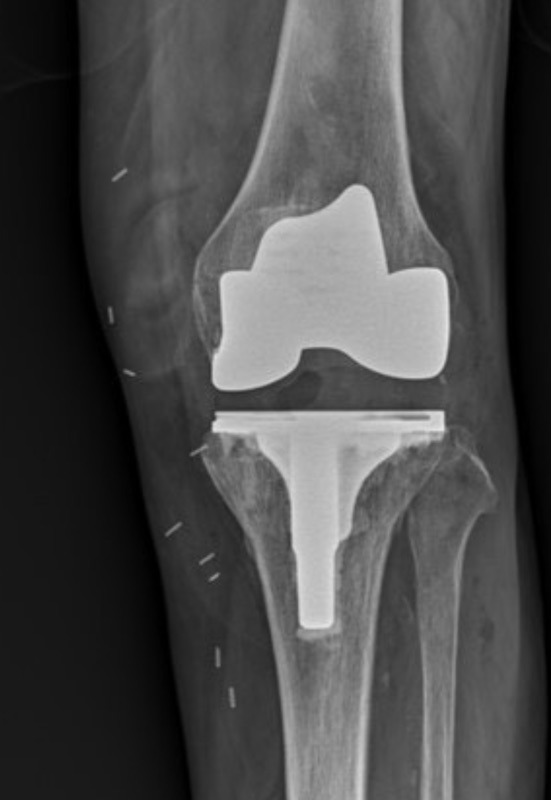

เป็นการผ่าตัดนำผิวข้อเข่าที่เสื่อมแตกออก แล้วใส่ผิวข้อใหม่ที่เป็นโลหะ–พลาสติกทางการแพทย์ที่แข็งแรงและปลอดภัย โดยไม่ต้องตัดกระดูกทั้งชิ้น แต่เปลี่ยนเฉพาะผิวข้อที่สึก

ข้อเข่าเทียมประกอบด้วย 3 ส่วนหลัก:

- ผิวข้อด้านบน (กระดูกต้นขา)

- ผิวข้อด้านล่าง (กระดูกหน้าแข้ง)

- แผ่นรองพลาสติกที่ช่วยให้ข้อเคลื่อนไหวลื่น

- เอกซเรย์พบข้อเข่าเสื่อมรุนแรง (ผิวข้อสึกหมด ช่องข้อแคบชิด)

4) ใส่ข้อเทียม

ใช้โลหะ–พลาสติกทางการแพทย์ที่เข้ากับร่างกายได้ดี